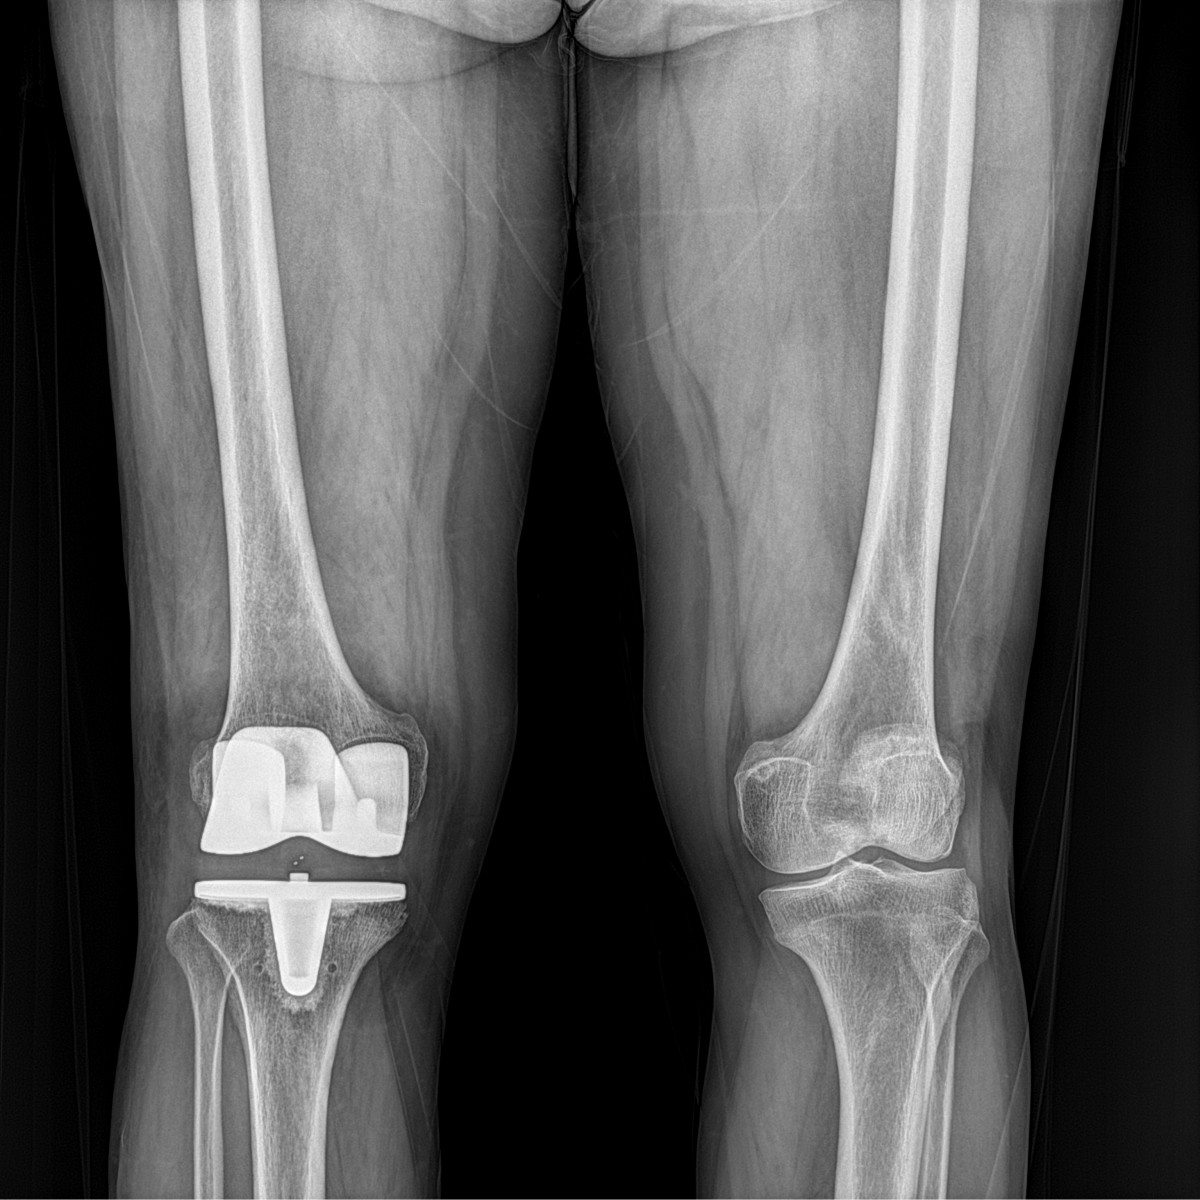

이재상원장님 무릎 인공관절 치환술 이영O 환자

dae765e4d9ac96aee867c9d6292d8784_1758010485_2221.jpg